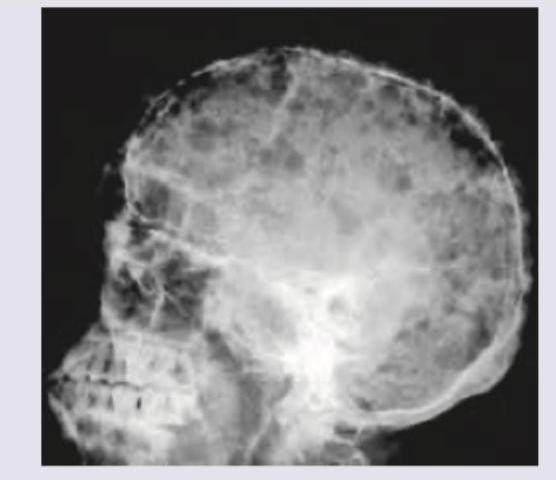

Identify the defect shown in the X-ray skull:

Explanation: ***Pepper pot skull*** - The image exhibits a diffuse punctate or granular demineralization of the skull, resembling a "pepper pot." This appearance is characteristic of **hyperparathyroidism**, where excessive parathyroid hormone leads to increased osteoclastic activity and trabecular bone loss, leaving behind small, lucent areas. - This pattern results from widespread erosions of the **cortical bone** and trabeculae throughout the skull, creating a mottled, finely granular or punctate radiolucency. *Crew cut appearance* - A "crew cut" or "hair-on-end" appearance is typically seen in patients with severe, chronic **hemolytic anemias**, such as **thalassemia major** and **sickle cell anemia**. - It results from extreme marrow hyperplasia, causing expansion of the diploic space and thinning of the outer cortical bone, leading to spiculation perpendicular to the skull surface. *Punched out lytic lesions* - "Punched out lytic lesions" are well-demarcated, rounded radiolucencies without a sclerotic border, classically associated with **multiple myeloma**. - These lesions represent areas of osteolysis caused by plasma cell infiltration and are typically larger and more discrete than the fine granular appearance seen in a "pepper pot skull." *Widened sella turcica* - A widened sella turcica is usually indicative of an intrasellar mass, most commonly a **pituitary adenoma**, or can be due to hydrocephalus. - This finding focuses specifically on the sella region and does not describe the diffuse, granular demineralization seen throughout the entire skull vault in the image.

Explanation: ***Pepper pot skull*** - The X-ray image displays a classic "pepper pot" appearance, characterized by diffuse **punctate lucencies** evenly distributed throughout the skull vault, resembling numerous small holes. - This finding is highly suggestive of **hyperparathyroidism**, where excessive parathyroid hormone leads to increased bone resorption, visible as demineralization and multiple small lytic lesions. *Artifacts* - **Artifacts** are extraneous marks or distortions on an image that do not represent true anatomical structures. - The observed pattern is a consistent, diffuse change in bone density, indicating a **pathological condition** rather than a technical error or imaging artifact. *Silver-beaten appearance* - A "silver-beaten" or **convolutional impression** refers to the undulating pattern on the inner table of the skull caused by increased **intracranial pressure** in children. - This appearance is characterized by broad, shallow indentations, which is distinct from the multiple small, sharply defined lucencies seen in pepper pot skull. *Hair-on-end appearance* - The **hair-on-end** or "crew-cut" appearance shows **perpendicular bony trabeculae** radiating outward from the skull vault, creating a spiculated pattern. - This finding is classically associated with **chronic hemolytic anemias** (thalassemia, sickle cell disease) due to marrow hyperplasia, not the diffuse lucencies seen here.